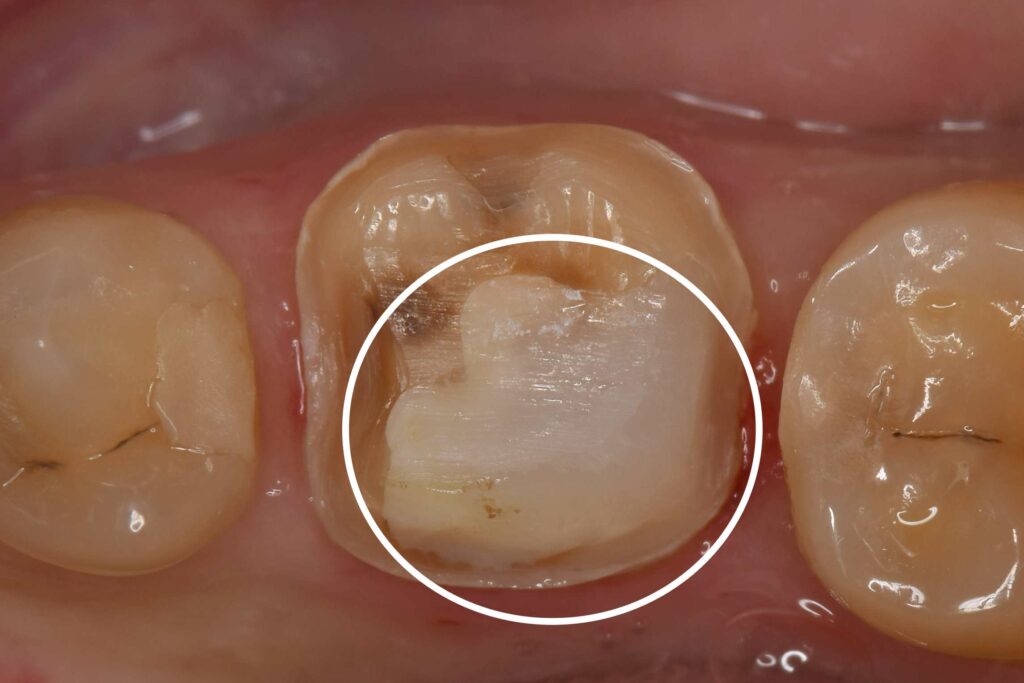

白丸はMTA治療後の部位です。広範囲にわたる虫歯があったことが分かります。

昔の銀歯の下に大きな虫歯があるとのことで来院されました。

レントゲン検査にてMTAを用いた歯髄温存療法の適用であると判断し、治療の概要、メリットデメリットをお話ししたところ患者様は本治療を希望されました。